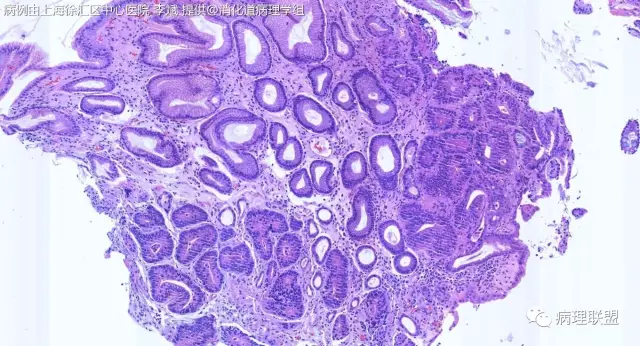

@李斌,高级别,腺体结构乱复杂,核异型性大,极向乱

@左淑英 子宫内膜受激素周期影响,腺体结构和上皮变化比较大,消化道受损伤、炎症等影响比较大,同样要看结构、看细胞,但标准确实不大一样。虽然具体病例需要具体分析,但我感觉在胃肠道,对于判断时感觉模棱两可的病例,表面成熟现象是区分反应性增生和低级别异型时可重复性相对比较好的指标;核极向是区分高低级别异型增生时可重复性相对比较好的指标。供参考

@石雪迎 谢谢石老师,胃粘膜腺体也遵循它的增生规律,表面成熟现象是个好标准,通俗易懂,再次感谢您,敬爱的石老师!